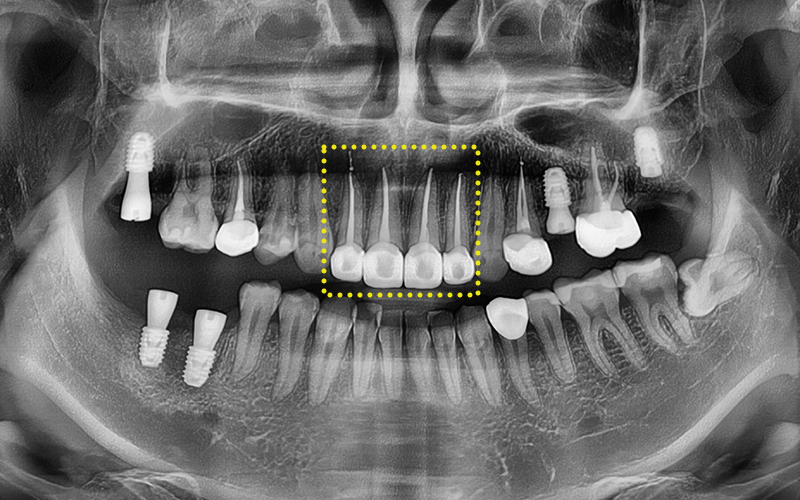

실제로 진료기록에서도 확인되듯이

10개가 넘는 치아에 대해

신경치료(근관치료)를 받으셨고,

대부분 복잡한 염증과 신경 감염이

동반되어 있었습니다.

특히 윗니 앞니와 어금니까지

넓은 범위에 걸쳐

치료가 진행되었습니다.

파노라마 사진을 촬영해

정밀 체크를 진행하였고,

전체적인 치료를 계획하였습니다.